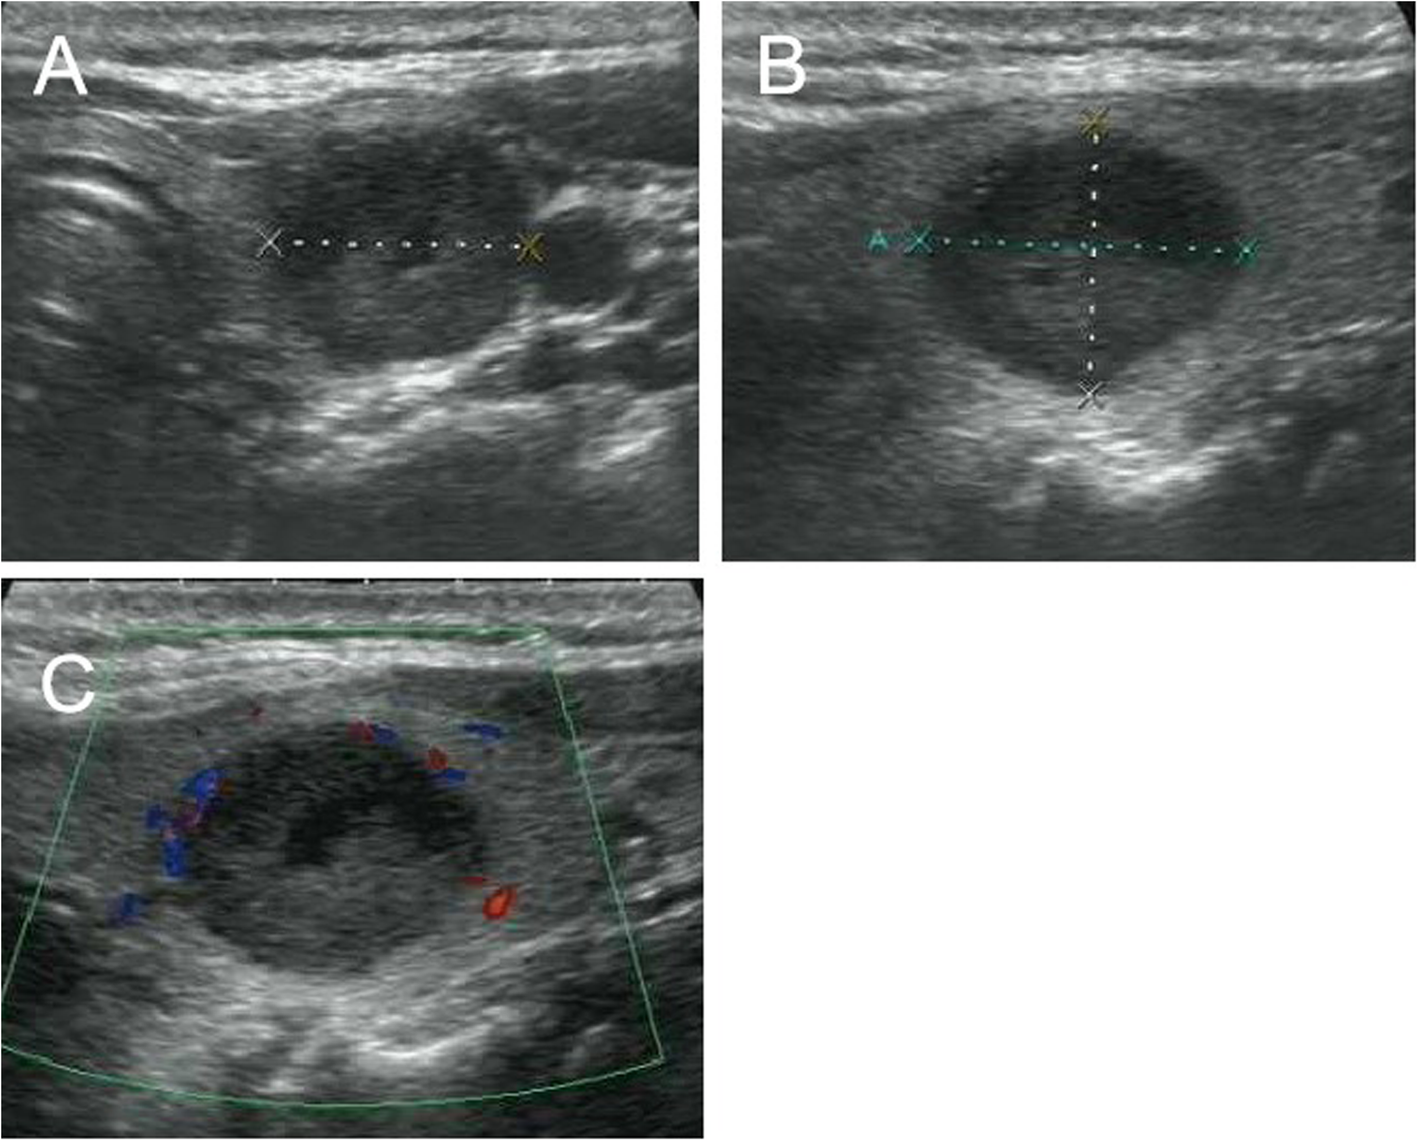

Fig. 6

From: Ultrasound features of medullary thyroid cancer as predictors of biological behavior

US images of medullary thyroid carcinoma nodules categorized by TI-RADS 3. Female patient, 48 years old, 1.8 cm × 1.4 cm × 1.4 cm. The serum calcitonin level was 960 pg/mL. a and b Lesion was solid with a little of fluid sonolucent area, hypoechoic, well-defined, ovoid to round in shape. a A/T < 1. c Absent blood flow